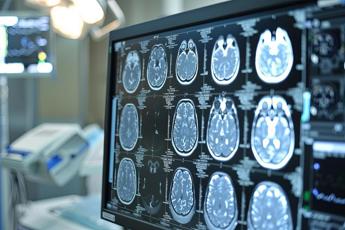

(Adnkronos) – E' la seconda causa di morte in Italia dopo le malattie ischemiche del cuore, oltre a rappresentare la prima causa di invalidità. L'ictus cerebrale, di cui oggi si celebra la Giornata mondiale, colpisce ogni anno nel nostro Paese oltre 130mila persone e si stimano in oltre 1 milione i pazienti con disabilità conseguente all'ictus. Una patologia correlata all'età, sebbene non siano rari i casi tra i giovani, anche a causa del consumo eccessivo e crescente degli stupefacenti. Il numero di casi aumenta con l'invecchiamento, coinvolgendo in particolare gli over 65. In alcuni casi l'ictus è preceduto da segni premonitori, i cosiddetti attacchi ischemici transitori o Tia, ovvero episodi di ischemia limitati nel tempo, caratterizzati da paresi, disturbi della parola o altri disturbi di breve durata seguiti da recupero completo. Purtroppo, però, nella maggior parte dei casi l'ictus è un evento improvviso e imprevedibile. Negli ultimi anni la cura dell'ictus, unitamente alla precocità nei soccorsi, consente di migliorare le possibilità di cura immediata e di ridurre il rischio di invalidità permanente. Per questo occorre fare molta attenzione ad alcuni segnali, come la paresi improvvisa di una gamba o di un braccio con perdita di forza, il calo della vista, un'improvvisa difficoltà nel parlare. In questo caso il tempo è fondamentale ed è importante raggiungere quanto prima un pronto soccorso per iniziare terapie trombolitiche. In Italia sono attive in tutte le regioni le Reti Stroke che vedono coinvolte le neurologie dei diversi ospedali, presso cui sono presenti équipe dedicate alla presa in carico delle fasi acute e subacute degli ictus. "In occasione della Giornata mondiale dell'ictus cerebrale, la Sin ribadisce l'importanza della neurologia, così come la necessità di avere anche nel nostro Paese un 'Piano nazionale dell'ictus' che consenta di effettuare diagnosi e trattamenti tempestivi, anche a distanza mediante la telemedicina, in tutto il territorio nazionale e che eviti ospedalizzazioni inappropriate o trattamenti inefficaci", dichiara il presidente della Società italiana di neurologia, Alessandro Padovani. "A testimonianza dell'importanza dei fattori di rischio e della concreta possibilità di una prevenzione in coerenza con il Piano nazionale One Health – sottolinea Padovani – negli ultimi anni vi è stata una riduzione dell'incidenza ovvero dei numeri di casi per anno. Quando invece i sintomi si manifestano in maniera acuta, è fondamentale raggiungere quanto prima un pronto soccorso per iniziare terapie trombolitiche. In Italia sono attive in tutte le regioni le Reti Stroke che vedono coinvolte le neurologie dei diversi ospedali presso le quali sono presenti équipe dedicate alla presa in carico delle fasi acute e subacute degli ictus". La Sin, unitamente alla Italian Stroke Association, quest'anno ha voluto inserire la Giornata mondiale dello Stroke tra le iniziative mirate a promuovere il proprio impegno nell'ambito della campagna One Brain, One Health a favore della salute del cervello. "Il nostro impegno – conclude Padovani – è quello di sostenere sempre iniziative di informazione e di conoscenza sull'ictus cerebrale, nella speranza che il nostro Paese sia presto all'avanguardia nella lotta contro tutte le malattie del cervello". —salutewebinfo@adnkronos.com (Web Info)